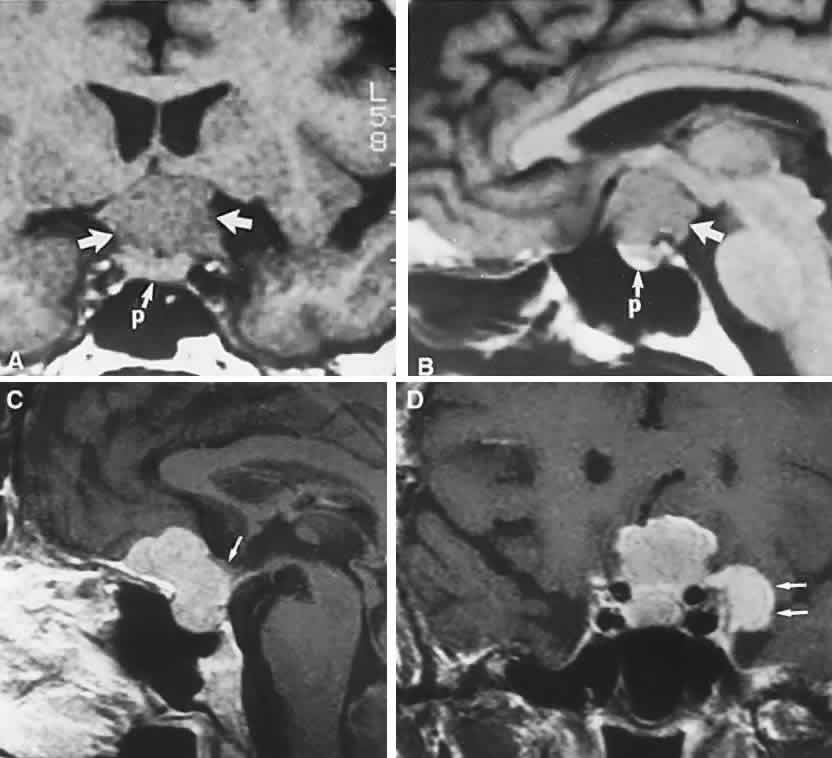

Fig. 4. Magnetic resonance imaging of a suprasellar meningioma (TR, 600 milliseconds; TE, 20 milliseconds). A. Coronal section of a large meningioma (large arrows), isodense to brain. B. Sagittal section. Note the normal sella and pituitary gland (p). Sagittal (C) and coronal (D) sections of a planum meningioma, extending into the sella. Note the upward deflection of the chiasm (arrow in C) and extension to the cavernous sinus (arrows in D).